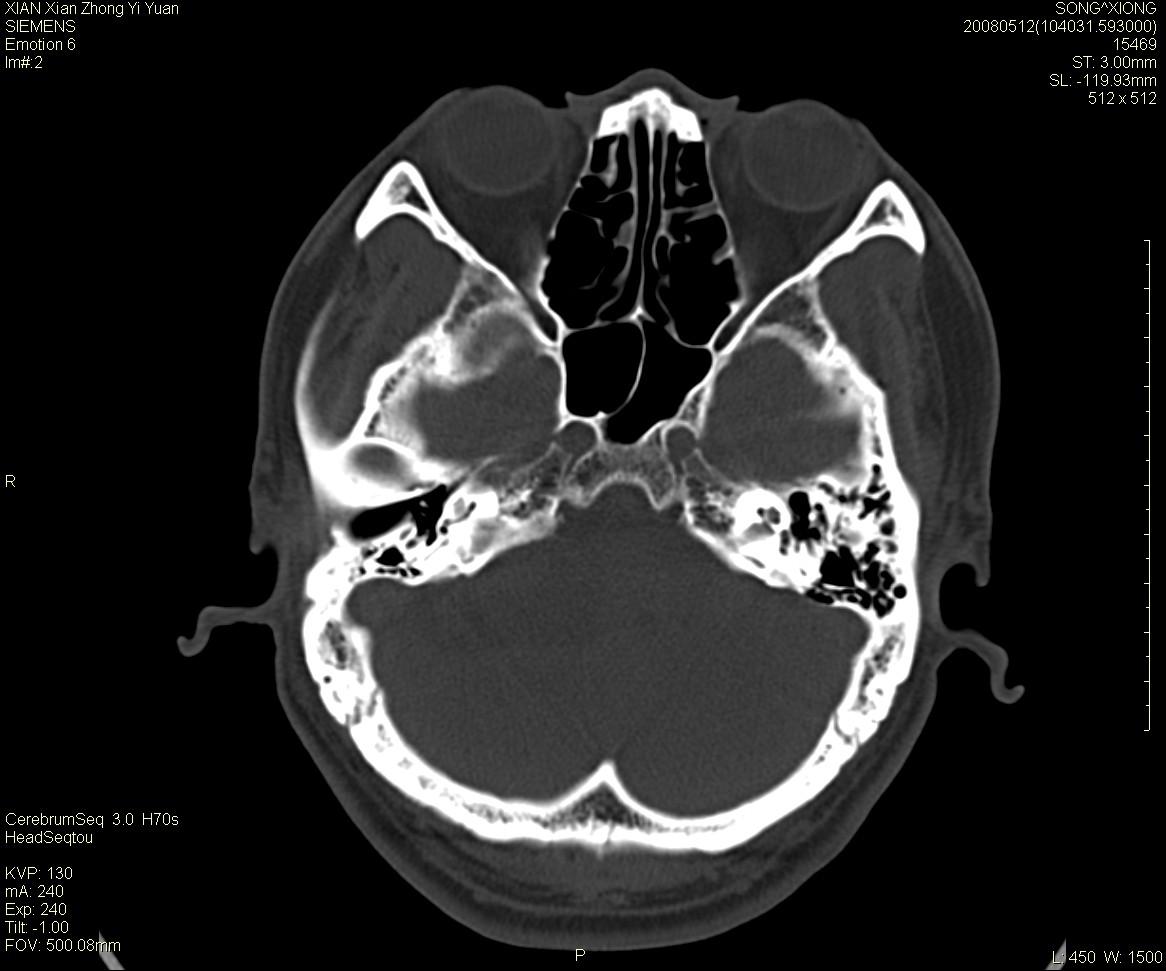

右侧内耳道慢性增宽,内耳道口出可见稍高密度影,桥小脑角池可见以较大低密度影,内缘较清,小脑、脑干、第四脑室受压、移位。

考虑:听神经瘤。

骨窗显示内听道扩大,考虑右侧听神经瘤

典型的右侧听神经瘤。